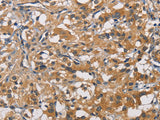

Applications IHC

IHC 1:50-1:200